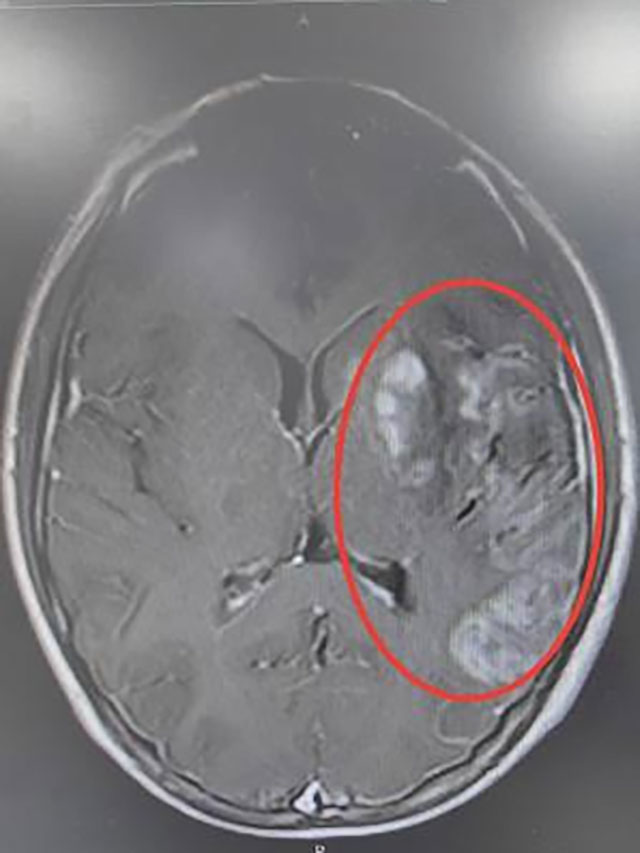

●头颅增强MRI:左侧额顶颞岛叶、基底节区、侧脑室旁及大脑中脚异常信号,部分病灶弥散受限,左侧外囊软化表现;

头颅MRI影像表现

最后考虑诊断为卵圆孔未闭合所致的脑梗死(心源性栓塞型),经中西医结合治疗后小王同学好转出院,并拟于后期接受卵圆孔未闭封堵术治疗。